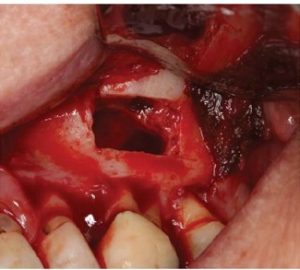

The cervical area of tooth LR3 was severely abraded. An intra -sulcular full-thickness muco-periosteal fap was raised; a vertical re leasing incision was positioned mesial to tooth LRI. The surgical stent was placed over the maxillary teeth (Figure 8) and a piezotome-guided surgical window wasdeveloped using the margins of the stent (Figure 9).

A chisel was used to elevate the cortical plate and root resection performed with Lindemann burs (Figure l0).

The cortical window was placed in sterile saline while the endodontic microsurgery was completed. After resection